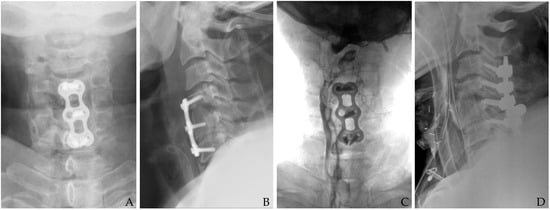

Anterior cervical spine surgery is a critical intervention for a variety of conditions ranging from degenerative disc diseases and traumatic injuries to neoplastic disorders. Although significant improvements have been achieved in surgical techniques, perioperative infection control, and postoperative care, the risk of postoperative infection remains a serious concern [1,2,3]. While the overall incidence of infection in cervical spine surgery is relatively low compared to lumbar procedures due to superior local vascularity and less extensive soft tissue dissection, the anatomical proximity of the cervical spine to vital neurovascular structures and the esophagus creates a high-risk environment for severe complications (Figure 1) [1,2,4,5].

Figure 1. The patient underwent C3-4-5 anterior cervical discectomy and fusion (A). At postoperative 2 months, postoperative infection occurred with retropharyngeal abscess (white arrows) and epidural abscess (B,C). Therefore, the patient underwent evacuation of retropharyngeal and epidural abscesses, irrigation/debridement, and revisional C5-6-7 corpectomy and fusion (D) and achieved a cure for the infection (E).